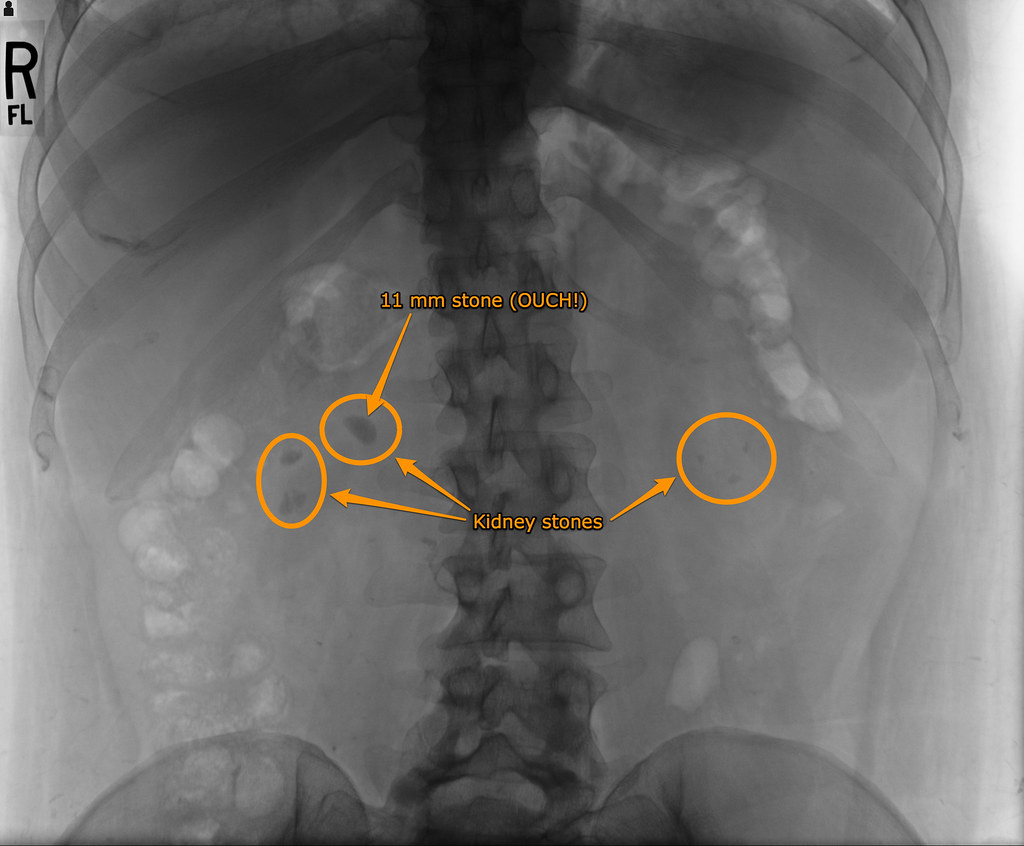

Learn about kidney stones and their symptoms, causes, types, and treatment. Kidney cysts can impair kidney function, although many are what are called simple cysts which do not result in health complications. Kidney stones are hard collections of salt and minerals often made up of calcium or uric acid. Symptoms & signs causes & stone types calcium. Symptoms include severe lower back pain, blood in urine, nausea, vomiting, fever, chills, and smelly or cloudy urine.

Kidney stones are hard collections of salt and minerals often made up of calcium or uric acid.

Despite with more than 200,000 new cases a year in the united states, kidney stones are an. Consuming certain things creates more waste that your. Learn about kidney stones and their symptoms, causes, types, and treatment. Kidney infections can usually be treated with antibiotics — but without treatment, they. Kidney cysts can impair kidney function, although many are what are called simple cysts which do not result in health complications. They form inside the kidney and can travel to other parts of the urinary tract. Your kidneys are powerful filtration systems that remove toxins from your blood to keep you healthy. Everything you need to know about what kidney stones are, what causes them to develop, and why some people are more likely to get them. Symptoms include severe lower back pain, blood in urine, nausea, vomiting, fever, chills, and smelly or cloudy urine. Some are as small as the period at the end o. Important to know is that not all kidney stones are alike. Here's an overview of what kidney cysts are. Symptoms & signs causes & stone types calcium.